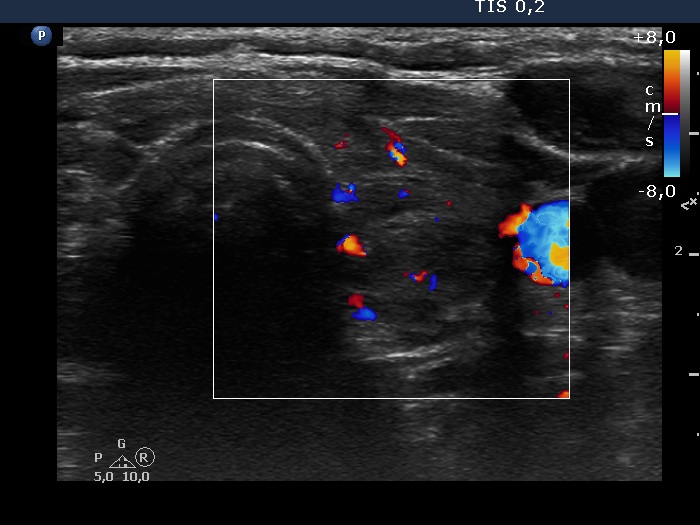

Consecutive patients with the final diagnosis of Hashimoto's thyroiditis - case 2 (23) (ultrasonographic picture 7)

Left lobe, transverse scan, color Doppler mode. The vascularization is not specific.